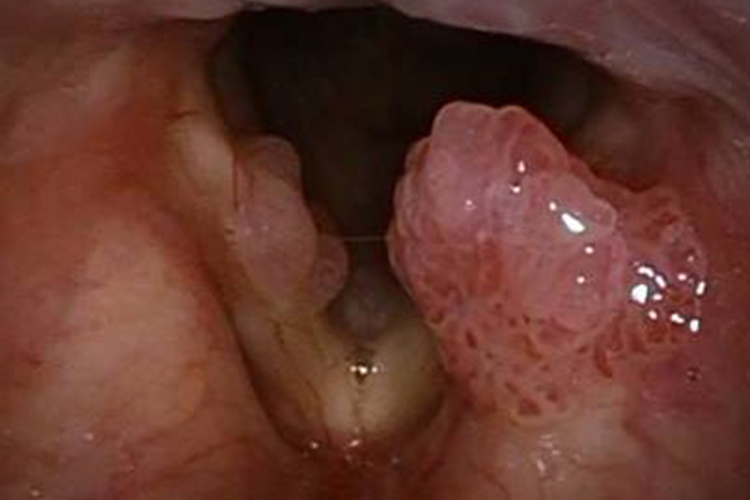

喉乳头状瘤:当机体声带前端出现喉乳头状瘤时,局部可表现为苍白、淡红色息肉,表面常呈桑椹状,粗糙不平。

喉癌:喉癌多发生于喉前部,悬雍垂旁可出现异常增生性物质,如出现菜花样、溃疡型息肉,喉头黏膜可有水肿,患者可伴有吞咽困难、声音嘶哑症状。